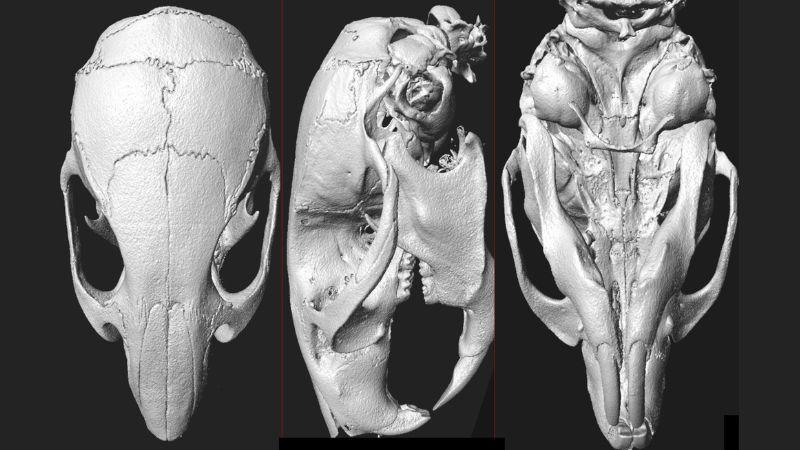

PCP DSI Telemetry EEG/EMG-Deep Brain EEG | PCI uCT-in vivo Imaging |

PCP DSI Telemetry EEG/EMG-Seizures | PCI uCT-ex vivo Imaging (Trabecular and Cortical Bone Quantification) |

PCP DSI Telemetry EEG/EMG-Sleep | PCI 2D Digital X-ray Skeletal Imaging |